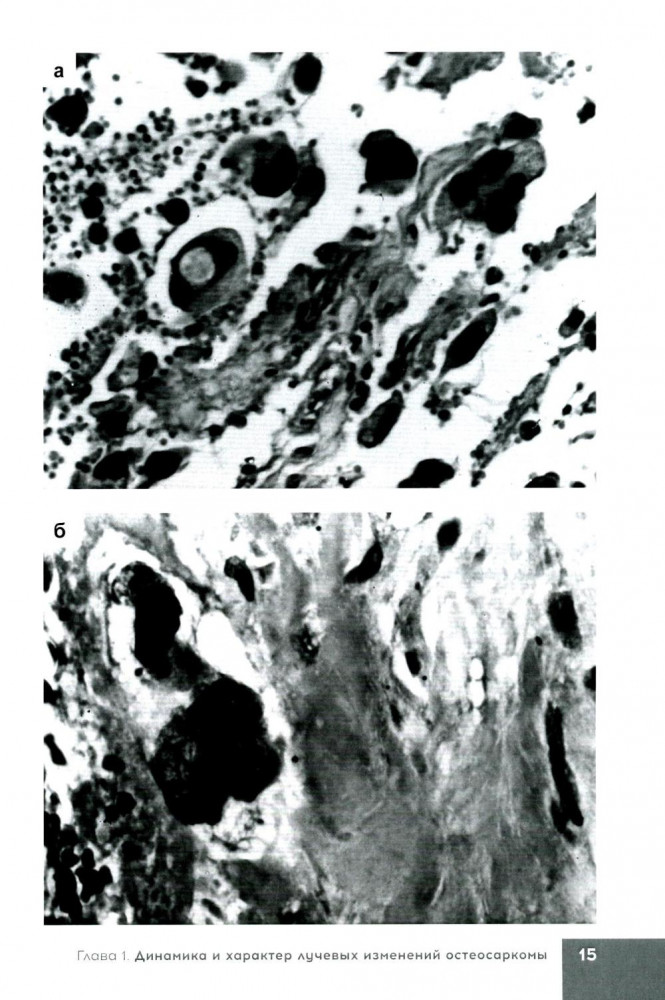

💳 Оплатить за товар можно при получении 🇰🇿 Есть бесплатная доставка по Казахстану от 1 дня 🎁 Копите бонусы с каждой покупки Серия: Библиотека цитолога В книге представлены возможности морфологических исследований (патолого-анатомических и цитологических) в определении морфофункционального состояния клеток и тканей двух типов первичных злокачественных новообразований костей до проведения, в динамике и после завершения курса лучевой терапии. Показана значимость использования полученных данных в выборе метода лечения, в т. ч. и лучевого, в оценке прогноза и эффективности лучевой терапии при злокачественных новообразованиях костей. |